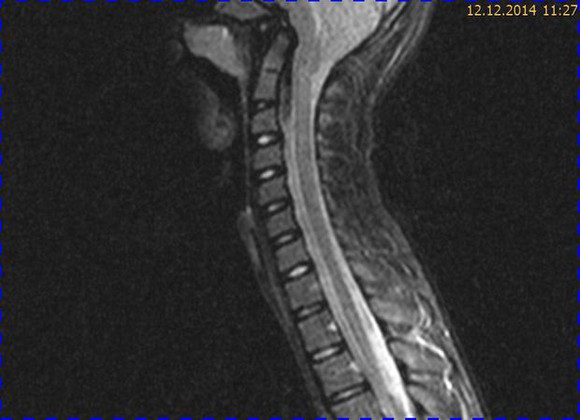

Abb. 2.1 Sagittales MRT (T2 TSE, 1,5 T): bei unveränderter Streckfehlhaltung der HWS 2 Monate nach der Erstuntersuchung Progredienz des Tonsillentiefstands, Syringomyelie

Abb. 2.2 MRT (T2 TSE transversal): obliteriertes Foramen magnum

Trotz weiterer Schmerz- und Physiotherapie konnte keine Beschwerdereduktion erreicht werden. 2 Monate später erfolgte eine MRT des Kopfes zum Ausschluss einer posttraumatischen Veränderung.

Bei dieser Untersuchung wurde übersehen, dass die Kleinhirntonsillen in das Foramen magnum disloziert waren und eine Arnold-Chiari-Malformation mit Erweiterung des 4. Ventrikels und des Aquäduktes inklusive Kleinhirntonsillentiefstand vorlag. Bei zwischenzeitlich auswärtig erfolgtem CT der HWS wurde eine Anlagestörung im kraniozervikalen Übergang beschrieben. Eine Kontrolluntersuchung des Kopfes weitere 4 Monate später dokumentierte neben einem medullären Ödem einen progredienten Tonsillentiefstand, der zur neurochirurgischen Behandlung mit operativer Erweiterung des Foramen magnum führte.